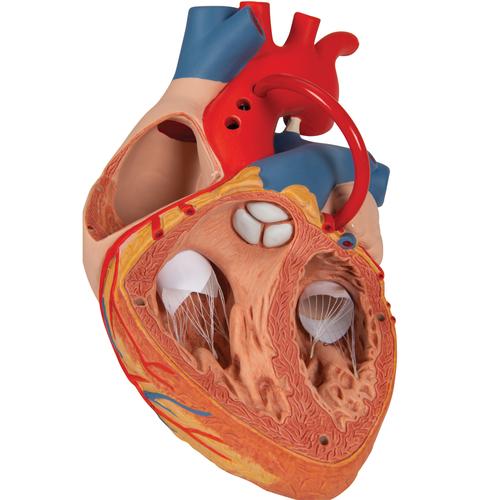

Фотографии и 3D-модели анатомии сердца человека